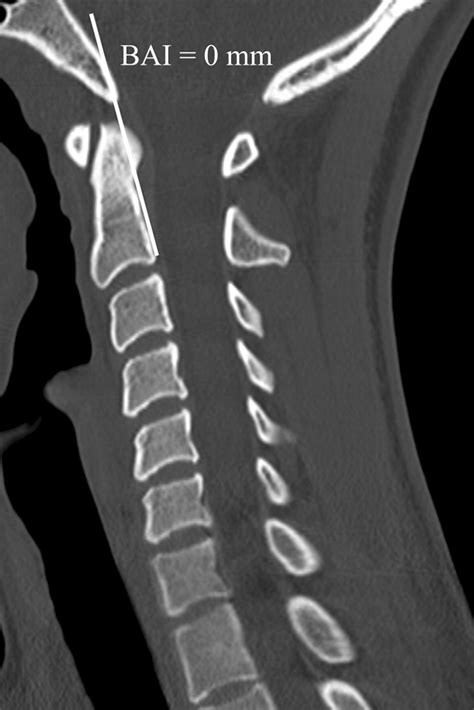

• Imaging Studies: Various imaging techniques are used to visualize the cranio-cervical junction. These may include:

CT Scans To provide detailed images of the bones and joints.